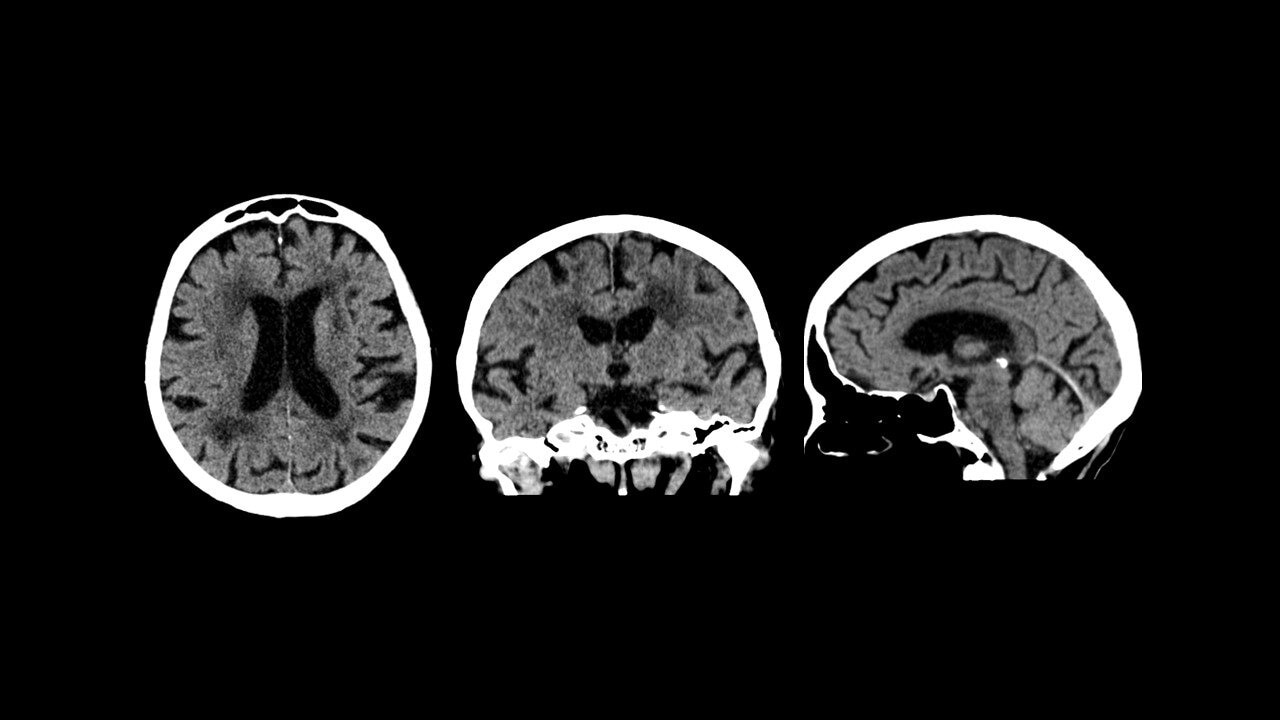

The highest sensitivity per cm in the market2 and scalability enable your PET/CT system to be optimized for both current and emerging tracers as well as for procedures beyond oncology such as cardiac and neuro imaging.

We built Omni Legend from the ground up to harness the power of digital dBGO, an innovative detector material with a small crystal size capable of producing high resolution images and exceptional image quality. This creates a brand-new category of detector technology that delivers more than two times the sensitivity than prior digital scanners,enabling fast scans5 at a lower dose.6 The end result is a remarkable design that’s more accessible to more people today and with a detector assembly engineered for future upgrades that allows for axial field-of-view scalability up to 128 cm.

The detector material at the core of the Omni Digital Detector takes PET/CT to the next level. Its high density and stopping power along with a 30 mm crystal depth make it possible to achieve an astronomical increase in NEMA sensitivity with up to 46 cps/kBq across a 32 cm axial field-of-view.4 This extreme rise in sensitivity goes beyond just providing for a higher quality image. Along with an exceptionally high NECR curve, it’s what may enable you to image high count rate tracers beyond FDG with the potential to increase the number of procedures your staff can execute, including procedures beyond oncology such as cardiac and neuro imaging.